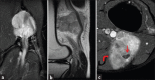

Magnetic Resonance Imaging Appearance of Schwannomas from Head to Toe: A Pictorial Review

Schwannomas are benign soft-tissue tumors that arise from peripheral nerve sheaths throughout the body and are commonly encountered in patients with neurofibromatosis Type 2. The vast majority of schwannomas are benign, with rare cases of malignant transformation reported. In this pictorial review, we discuss the magnetic resonance imaging (MRI) appearance of schwannomas by demonstrating a collection of tumors from different parts of the body that exhibit similar MRI characteristics. We review strategies to distinguish schwannomas from malignant soft-tissue tumors while exploring the anatomic and histologic origins of these tumors to discuss how this correlates with their imaging findings. Familiarity with the MRI appearance of schwannomas can help aid in the differential diagnosis of soft-tissue masses, especially in unexpected locations.